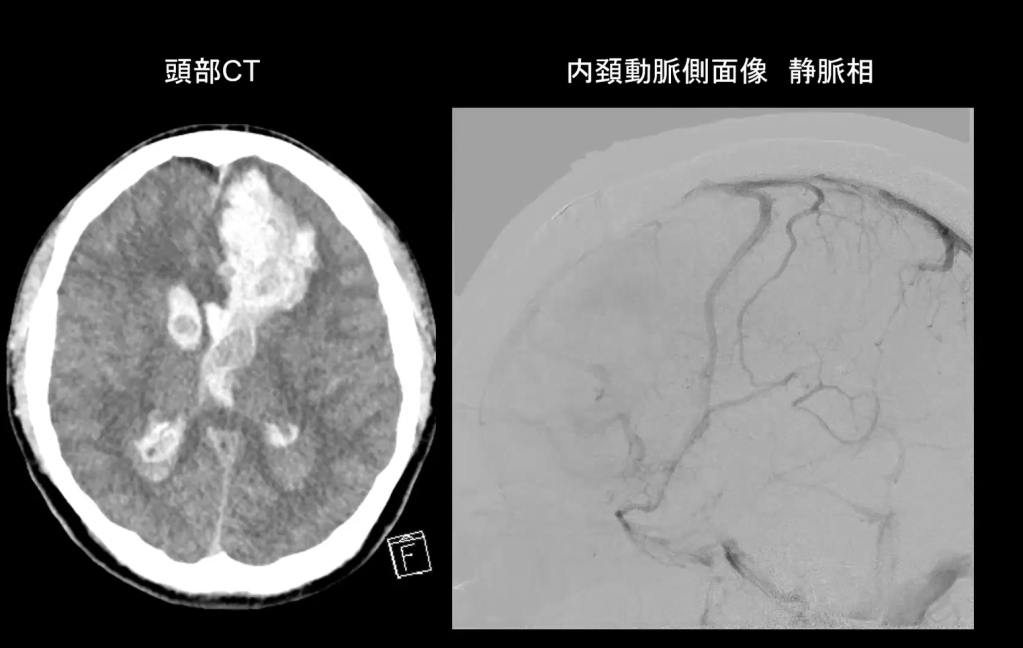

17:20 症例提示

武蔵野徳洲会病院脳神経外科、松崎粛統先生

東海大学八王子病院 青木吏絵先生

他